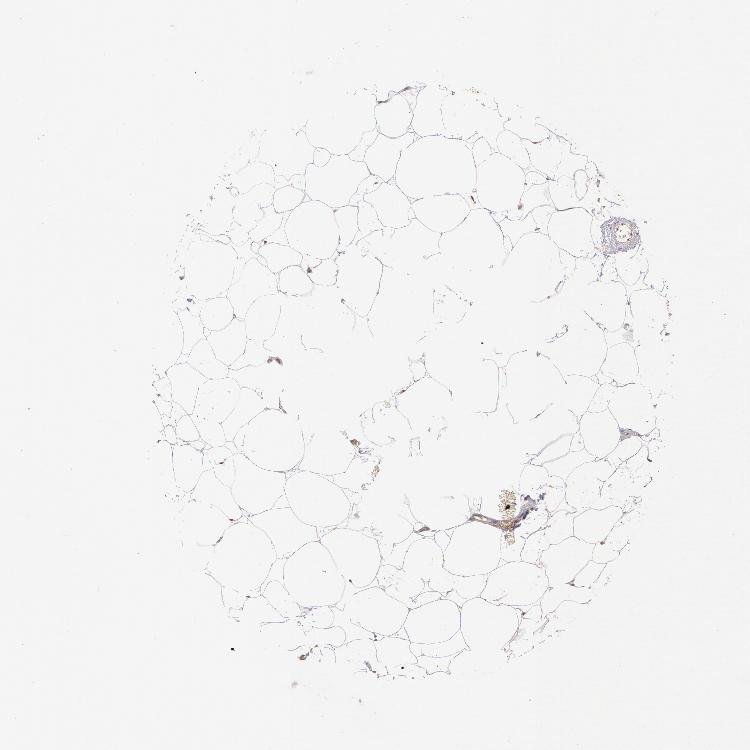

ADIPOSE TISSUE - Antibody stainingi

Antibody staining in the annotated cell types in the current human tissue is reported as not detected, low, medium, or high, based on conventional immunohistochemistry profiling in selected tissues. This score is based on the combination of the staining intensity and fraction of stained cells.

Each image is clickable and will lead to virtual microscopy that enables deeper exploration of all samples and also displays staining intensity scores, fraction scores and subcellular localization as well as patient and tissue information for each sample.

Antibody HPA000903Antibody CAB006244

Adipocytes MediumMedium